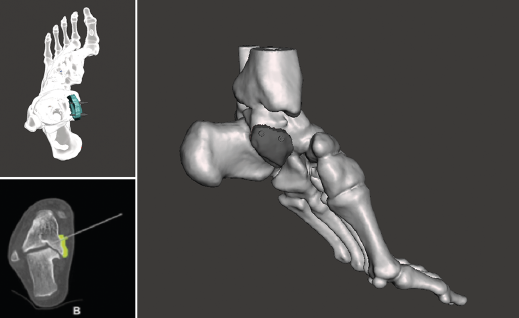

Figura 1. Fractura conminuta de la cúpula del astrágalo.

Figura 2. Modelo 3D del defecto del astrágalo.

Figura 3. Impresión de la guía 3D con el defecto del astrágalo y guía para su colocación.

Se trata de un paciente varón de 35 años que, tras una precipitación, presenta impotencia funcional en el miembro inferior. Tras la valoración clínica y radiológica, se observa un estallido de la parte posterior de la cúpula astragalina (Figura 1).

Utilidad de la impresión 3D: debido a la complejidad de la lesión, se decide tratarla con un aloinjerto estructural. Se decidió imprimir un modelo 3D del defecto óseo para poder tallar el injerto con la forma más parecida al defecto original.

- Obtención de la forma real del defecto combinando el astrágalo con una imagen especular del astrágalo contralateral (Figura 2).

- Impresión 3D del defecto del astrágalo y guía para la colocación de las agujas (Figura 3).